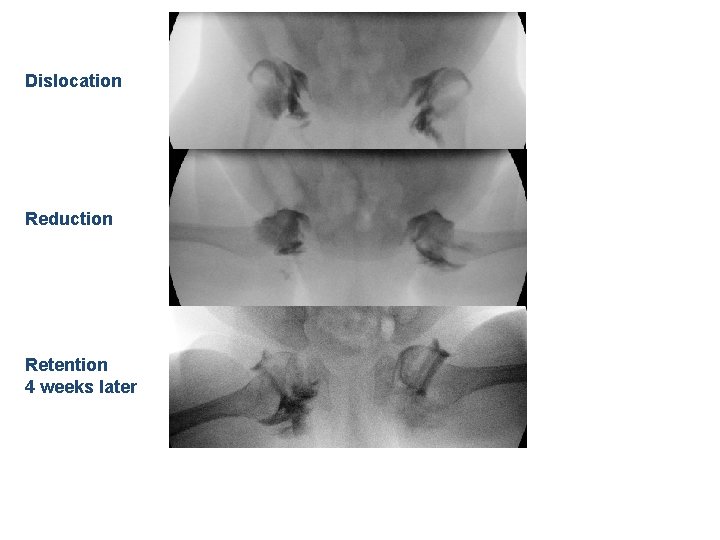

Dislocation Reduction Retention 4 weeks later